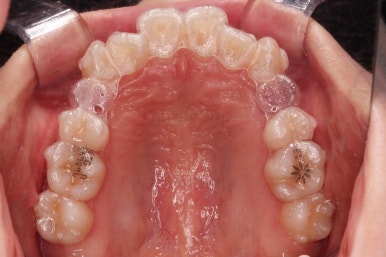

어금니쪽을 잘 보시면 별표? 혹은 꽃모양 무늬가 그려진게 보이실텐데요.

이 그림이 있는게 인비절라인 정품입니다.

발치 공간이 서서히 모이며, 치아도 가지런해지고 있고 앞니 뻗침도 점점 잡히고 있어요.

교합이 안정되었고, 치열도 가지런해졌으며 앞니 각도나 덧니 부분도 상당히 좋아졌어요.

부산교정전문의 전후 사진을 비교해 볼게요.

발치교정치고는 비교적 짧은 기간인 20개월만에 치열, 교합, 뻗친 느낌, 원하는 만큼의 입매 등 많은 점이 잘 개선된 치료였습니다.